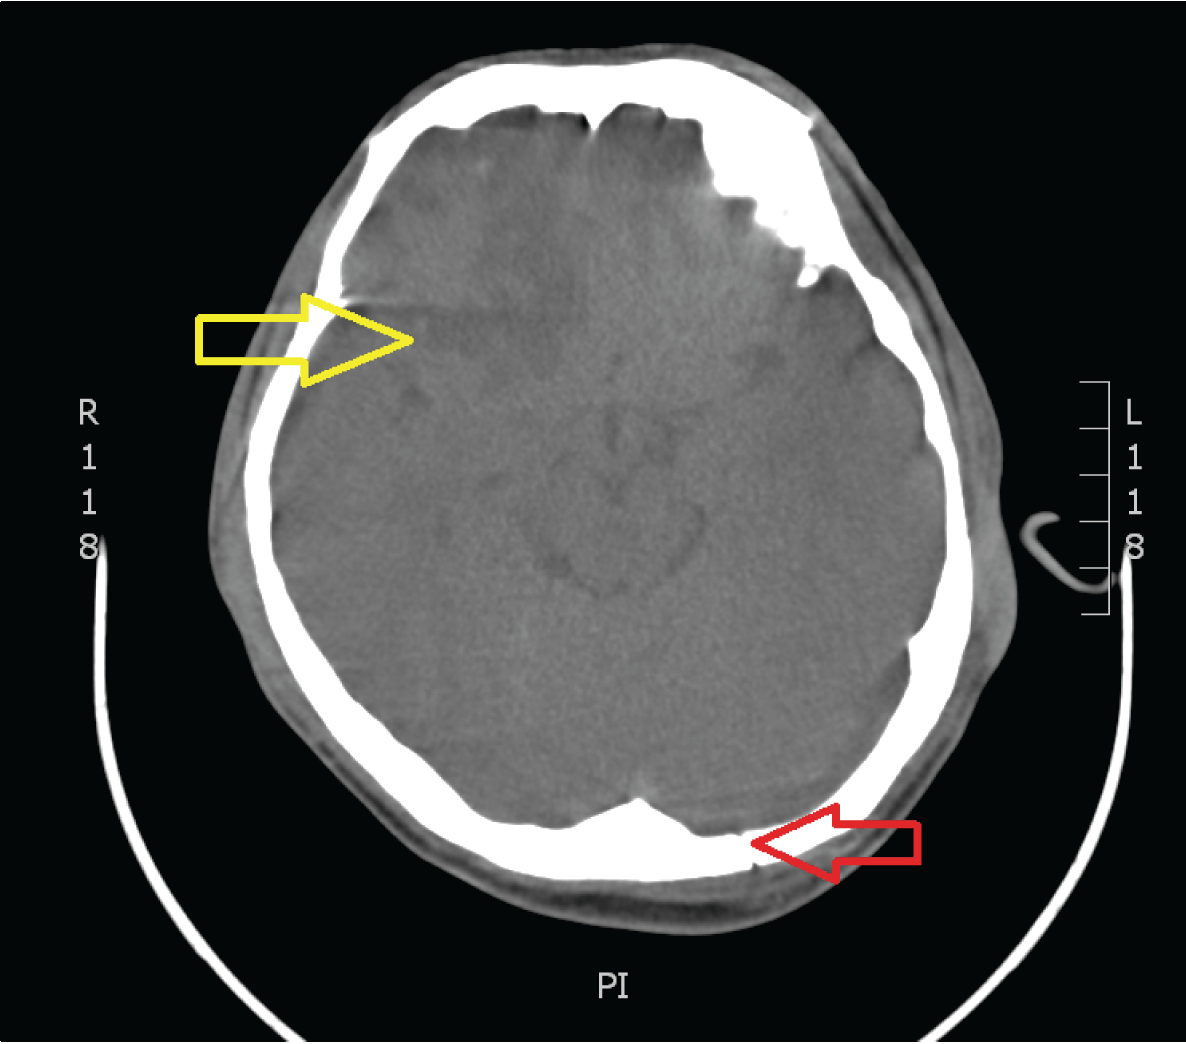

Computed tomography scan brain showed occipital skull fracture and hemorrhage over right frontal and left frontotemporal. (Figure 1)

Figure 1: Occipital skull fracture (red arrow) and hemorrhagic contusion both frontal lobe with surrounding oedema (yellow arrow).